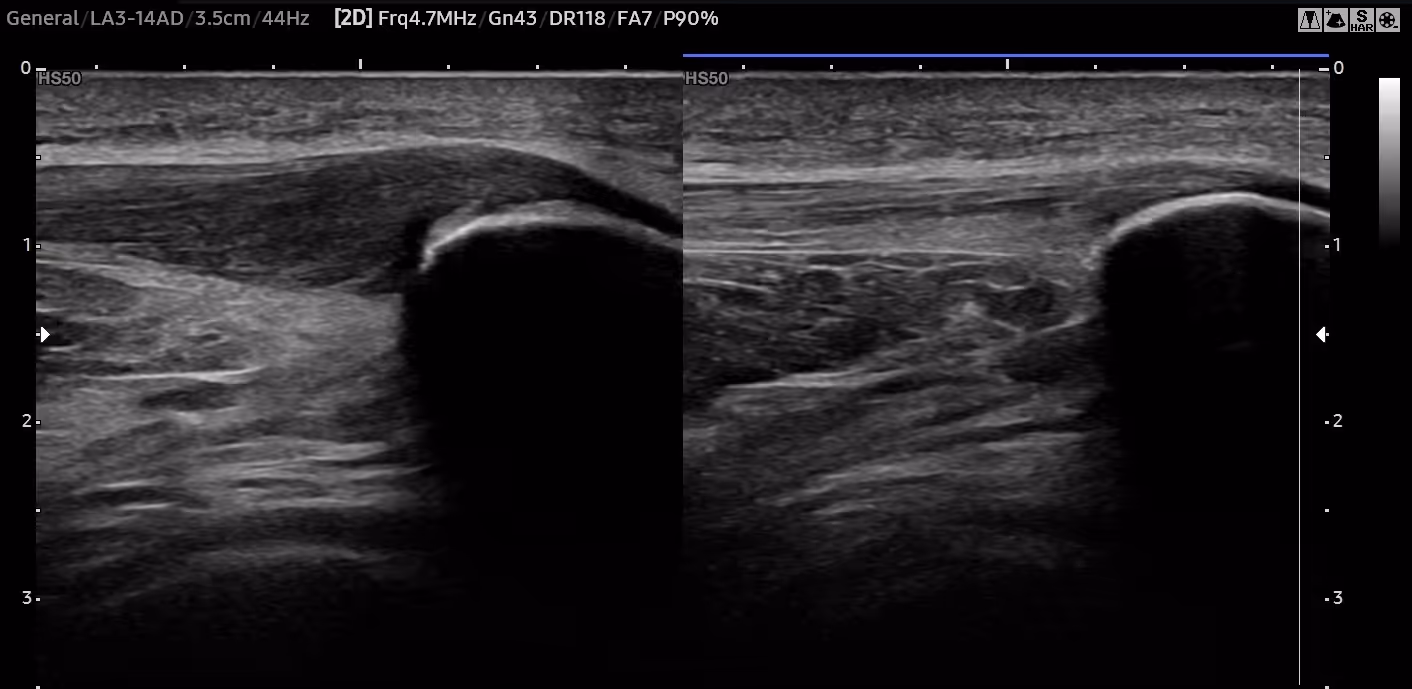

Ved patellartendinopati skjer det endringer i senens oppbygning. Selv om man tidligere kalte dette for senebetennelse, er det egentlig en tilstand der senen gradvis brytes ned heller enn at man ser en betennelse i ordets rette forstand. De fine, velorganiserte fibrene i senen blir mer rotete og uorganiserte. Dette gjør at senen blir svakere, noe som kan føre til smerter og gjøre det vanskeligere å bruke kneet normalt.

Tendinopati betyr "sykdom i senen" og referer til flere skademekanismer som f.eks. partielle (delvise) rupturer, små rifter, eller slitasjeendringer i senevevet. Disse kan oppstå akutt, på grunn av overbelastning eller på grunn av aldersbetingede endringer i senen. Uavhengig av skademekanisme fører dette til at senen blir tykkere, stivere og mindre elastisk.